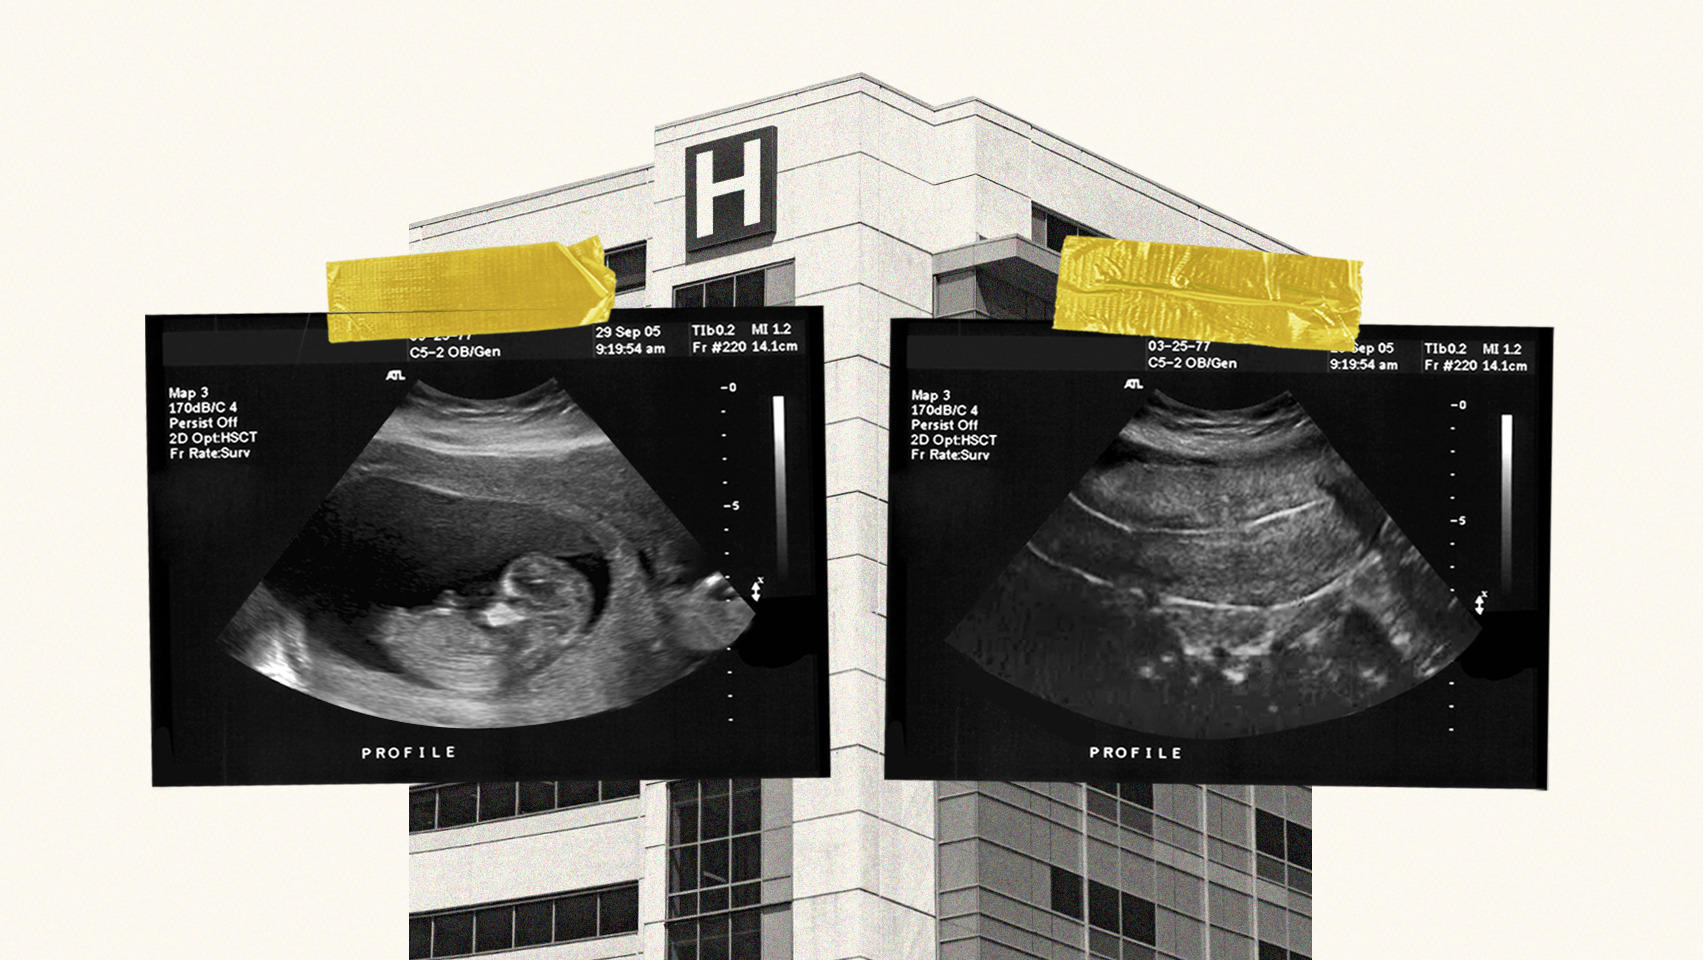

El PP impulsará una lista de médicos dispuestos a practicar abortos para no señalar a los objetores de conciencia